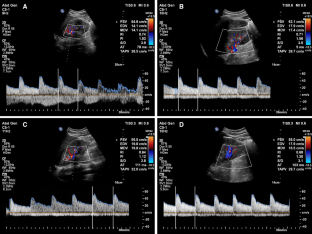

Fig. 2